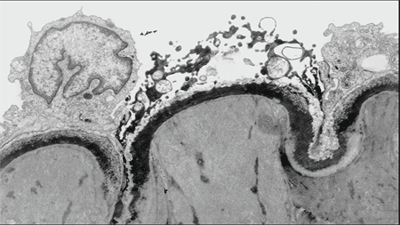

Базальная секреция соляной кислоты (циркадный процесс, который подчиняется холинер- гической регуляции через блуждающий нерв и гистаминергической - через локально выделяющийся гистамин) повышена, как правило, у больных, перенесших стресс. Важнейшим физиологическим стимулятором секреции кислоты является пища. Основные стимуляторы секреции кислоты в желудке - гистамин, гастрин и ацетилхолин. Многие факторы угнетают секрецию кислоты, наиболее важными среди них являются простагландины и соматостатин. Как стимуляторы, так и ингибиторы процесса секреции кислоты в желудке действуют через специфические рецепторы, находящиеся на обкладочных клетках. Гистамин, выделяющийся в основном из энтерохромаффинных клеток слизистой оболочки желудка, стимулирует секрецию кислоты через Н2-рецепторы, связанные с циклической АМФ (цАМФ). Гастрин и ацетилхолин активируют специфические рецепторы, связанные с системой «кальций /протеинкиназа С» [23,41,73,74]. Исследования, проводимые на протяжении последних лет, подтвердили высокую значимость дисбаланса цитокинов, концентрации которых резко повышаются при тканевом повреждении любого генеза, в развитии вторичных повреждений ЖКТ, при которых фактор некроза опухолей (ТNF), интерлейкины (IL-1, IL-8) и целый ряд других цитокинов, относящихся к провоспалительным медиаторам, способны выс-вобождаться в системный кровоток и вызывать дистанционное повреждение во многих органах (в том числе - ЖКТ). Было доказано, что указанный механизм может быть вовлечен в патогенез синдрома спланхической гипоперфузии, а также участвовать в гипотонии и атонии кишечника [7,18,86]. Нестероидные противовоспалительные средства, широко используемые в травматологической практике, являются важным повреждающим фактором для слизистой оболочки желудка и двенадцатиперстной кишки, поскольку эти препараты угнетают выработку простагландинов -необходимых факторов защиты слизистой оболочки [49]. Уже через несколько часов после развития критического состояния при эндоскопическом исследовании желудка становятся заметными субэпителиальные петехии (рис.2), часть из которых способна быстро прогрессировать в эрозии и язвы (рис.3). По истечению суток эрозивный гастрит и стрессорные язвы желудка выявляются уже у 74-100% пациентов ОРИТ, имевших эпизод острой гипоксии. В типичных случаях петехии локализуются в области дна желудка. В пилорическом отделе повреждения мукозного слоя формируются реже и позднее, чем фундальные, но, как правило, охватывают более глубокие слои [76, 82,86].

| Рис. 2. Эрозивный гастрит | 3. Язва желудка |